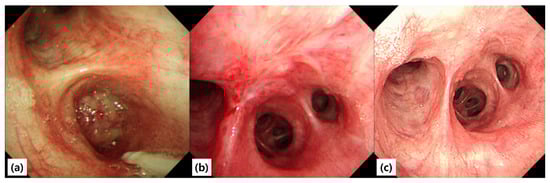

Background and Clinical Significance: Endobronchial leiomyoma is a rare benign tumor of the respiratory tract, accounting for less than 2% of all benign pulmonary neoplasms. Most cases have been treated surgically or with endoscopic modalities such as laser or rigid bronchoscopy-assisted cryotherapy. Flexible bronchoscopic cryoextraction has been rarely reported, typically with 2.2-mm probes. Small-caliber cryoprobes (1.1- and 1.7-mm) have been validated for diagnostic transbronchial cryobiopsy but not for therapeutic removal of leiomyoma. We report a case of complete removal of endobronchial leiomyoma using a 1.7-mm cryoprobe via flexible bronchoscopy, demonstrating full airway and physiologic recovery. Case Presentation: A 25-year-old never-smoking man was referred after an abnormal health-screening chest radiograph demonstrated right middle and lower lobe atelectasis. Chest CT revealed a mass obstructing the proximal bronchus intermedius. Spirometry showed reduced FEV1 and FVC with preserved FEV1/FVC ratio, consistent with central airway obstruction. Therapeutic flexible bronchoscopy (Olympus BF-1TQ290) was performed under endotracheal intubation. Initial forceps biopsies were followed by transbronchial cryobiopsy with a 1.7-mm cryoprobe, applied for five freeze–adhesion cycles. The mass detached en bloc and was retrieved without complications, resulting in complete airway recanalization and visualization of the right middle and lower lobe bronchi. Histopathology showed interlacing fascicles of bland spindle cells with cigar-shaped nuclei, positive for SMA and desmin and negative for S-100 and CD34, confirming leiomyoma. The patient was discharged the next day. At one-year follow-up, bronchoscopy and CT demonstrated no recurrence, and spirometry normalized. Conclusions: Reports combining flexible bronchoscopy with a 1.7-mm small-caliber cryoprobe for en bloc removal of endobronchial leiomyoma are rare. This technique may represent a minimally invasive option for selected cases, provided careful hemostatic planning and appropriate case selection. Full article

Figure 1